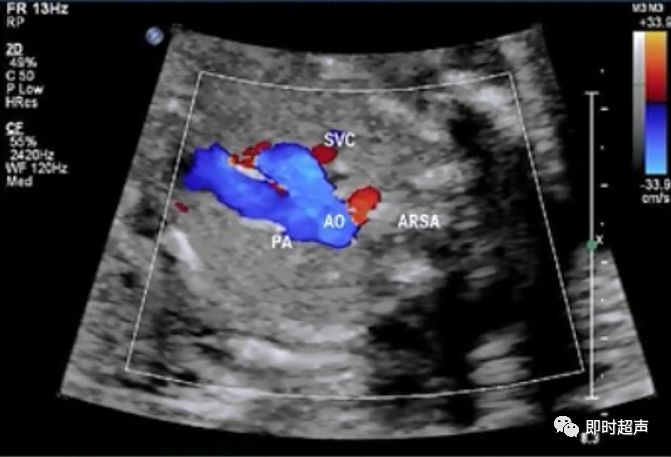

- 迷走右锁骨下动脉

迷走右锁骨下动脉

如何鉴别奇静脉和迷走右锁骨下动脉

- 多普勒频谱

- 观察清楚起止部位